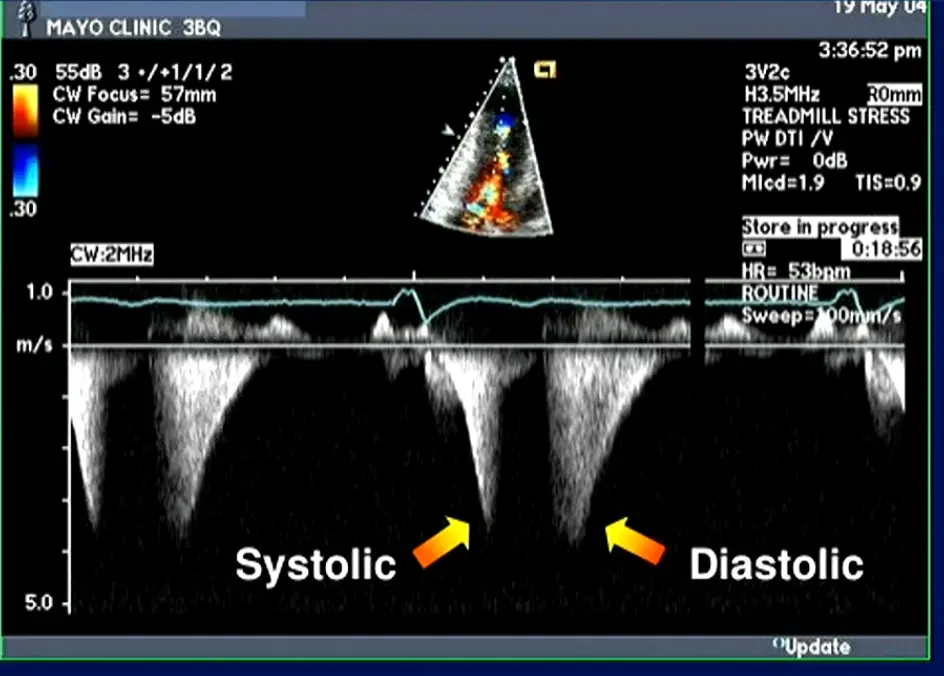

- MR jet characteristics can be useful to tease out if 1˚ or 2˚ MR

- MR caused by SAM is typically mid-to-late systolic in timing and posterior or lateral in orientation, owing to the anterior distortion of the mitral valve and compromised leaflet coaptation.1

- 📝 central and anterior jets may also result from SAM of the mitral valve.

- If anterior/centrally directed jet, then maybe it isn’t just the SAM that’s the problem

- Posteriorly-directed MR jet (classically): Usually, the anterior and posterior MV leaflets fail to coapt in mid-late systole, due to the upward and anterior motion of the anterior leaflet toward the LVOT, creating a funnel that directs the MR posteriorly through the interleaflet gap.2